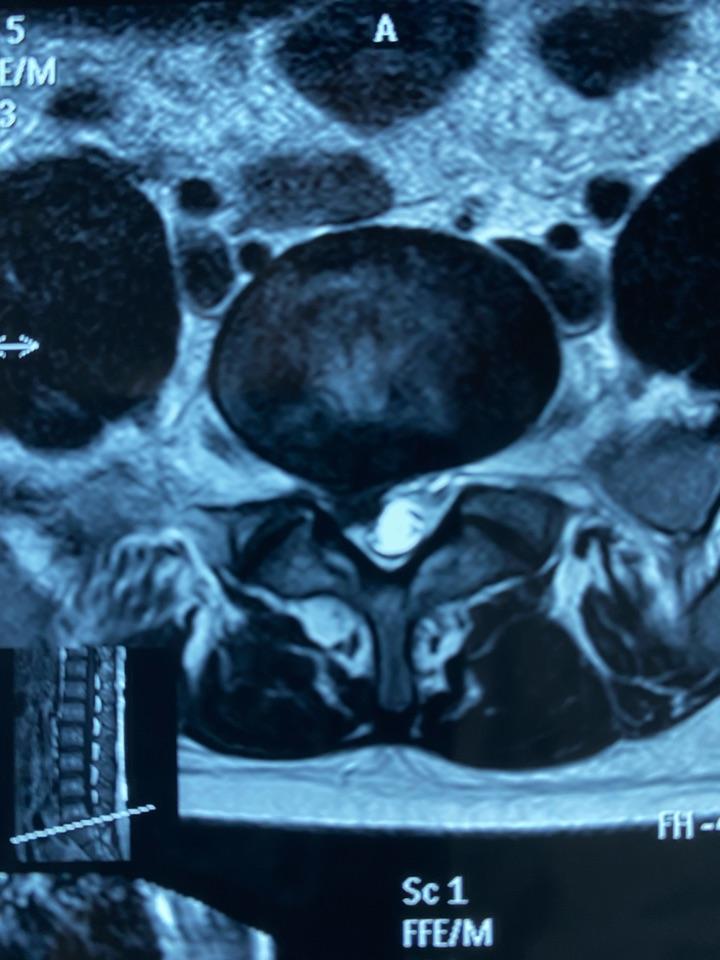

腰椎磁共振平扫:右侧神经根严重受压